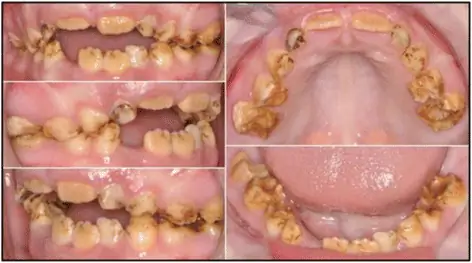

Лиственные зубы при гипоплазии эмали самоеда являются нормальными, но аномалии появляются у взрослых зубов сразу после прорезывания. Ранним признаком расстройства является неприятный запах изо рта. На рисунке 4 показан типичный вид зубов самоеда с наследственной гипоплазией эмали у собаки, которая регулярно получала стоматологическую помощь. Зубы обесцвечиваются, а поверхности в тех местах, где эмаль либо отсутствует, либо тонкие. Зубы часто притупляются, а промежутки между зубами увеличиваются из-за истончения слоя эмали. Тартер и зубной камень имеют тенденцию быстро накапливаться на нерегулярных поверхностях зубов при отсутствии обычной стоматологической помощи (рис. 5). Гингивит и припухлость десен является распространенной сопутствующей проблемой (рис. 5) и часто прогрессирует до более прогрессирующего заболевания пародонта. Может возникнуть кариес, который может распространяться на пульпу зуба. Потеря зубов может произойти из-за серьезных ссадин, переломов и сопутствующих инфекций корня зуба.

Самоеды с типичными поражениями наследственной эмали, гипоплазией. Зубы заметно обесцвечены; меньше, притуплено и дальше друг от друга; поверхности зубов нерегулярны. Эта собака регулярно получает стоматологическую помощь и, следовательно, зубной дегустатор практически отсутствует, а десны остаются здоровыми

Самоеды с гипоплазией эмали и обесцвечиванием зубов, чрезмерным скоплением дегтя и опухшими деснами вследствие заболевания десен